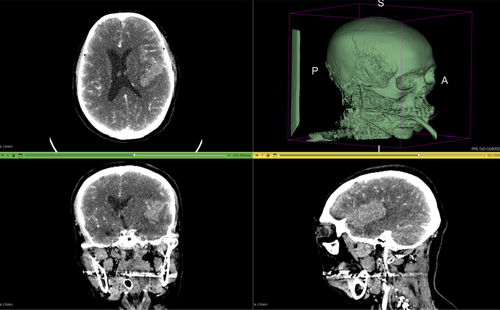

당사는 수술계획, 교육을 위한 의료용 XR 콘텐츠와 재활을 위한 게임화 콘텐츠, 실내 항법을 위한 AR 콘텐츠 등 다양한 XR 콘텐츠를 제작 공급하고 있습니다.

인공지능과 확장현실 기술을 활용하여 건강해서 병원에 가기 전에는 미리 점검을 해서 건강을 유지하고, 병원에 갈 일이 생긴 후에는 환자, 보호자 및 의료인들에게 이해를 돕고, 치료나 수술 후 일상으로의 복귀가 자연스럽도록 도움으로써 우리의 사명을 수행하고자 한다.